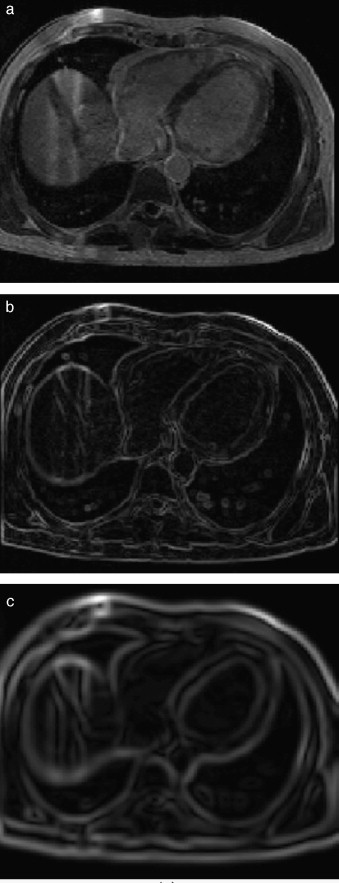

En la figura 7 se presenta la aplicación de dos rutinas del cálculo del gradiente en IRM cardiovascular. Obsérvese como los contornos son mejorados y se puede distinguir mejor el músculo miocardio y el ventrículo izquierdo. En la figura 7 .b se aplicó el operador Sobel en las direcciones x,y,z. En la figura 7 .c se presenta el resultado de aplicar el filtro itk::GradientMagnitudeRecursiveGaussianImageFilter[20]. Este filtro calcula la magnitud de la imagen gradiente por cada pixel o voxel. El proceso computacional consiste en primero suavizar la imagen a través de la convolución con una máscara Gaussiana y luego aplicar el operador diferencial.

|

|

|

Figura 7. Aplicación de las rutinas de módulo de una imagen gradiente. (a) IRM cardiovascular original, solo se visualiza el corte axial número 33. (b) Aplicación del operador Sobel en x,y,z en la imagen (a). (c) Imagen módulo del gradiente de (a) empleando itk::GradientMagnitudeRecursiveGaussianImageFilter . |

En la figura 8 se presenta la aplicación de la rutina del filtro sigmoid a partir de la imagen módulo gradiente mostrada en la figura 7 .c.

|

|

|

Figura 8. Reforzado de bordes empleando el filtro sigmoid . (a) Imagen módulo gradiente de IRM cardiovascular l. (b) Imagen (a) con los bordes reforzados empleando en itk::SigmoidImageFilter . |